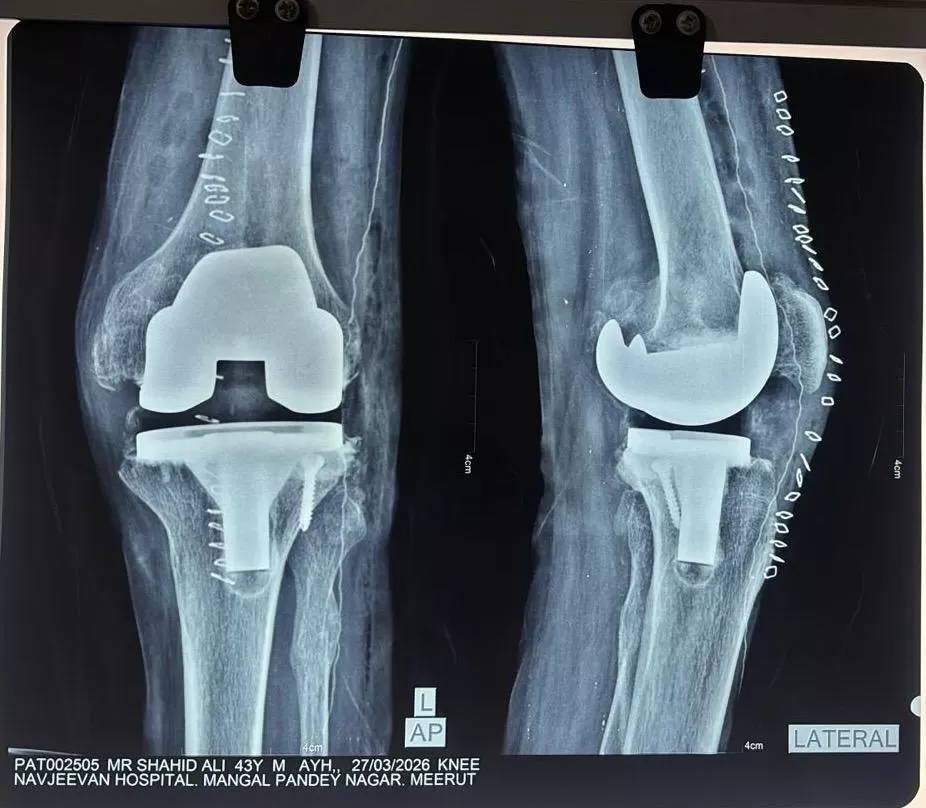

TKR (Total Knee Replacement)

Shahid

Name: Shahid

Date of Operation: 25 March 2026